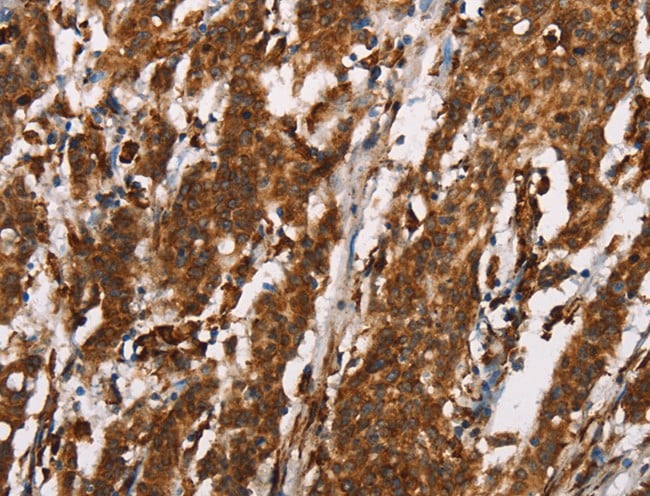

IHC (Immunohistochemistry)

(Immunohistochemistry of paraffin-embedded Human gasrtic cancer tissue using CTAG1A/B Polyclonal Antibody at dilution 1:25)